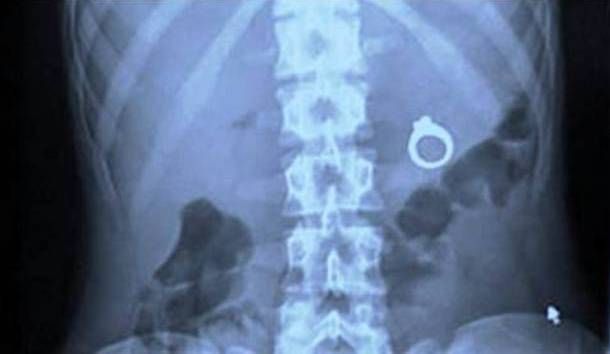

Objects that are swallowed or inserted through the rectum may enter the alimentary tract, which is the passage between the mouth and the anus.

Some items are small enough that the body will expel them naturally, but others are large enough that they may cause intestinal blockage. An x-ray or CT scan may be required to determine the exact location and movement of the foreign body, which will help doctors determine whether they need to surgically remove the object.

If the item is small but potentially harmful, such as a button, battery or a magnet, doctors may decide to remove the foreign body before it causes damage.